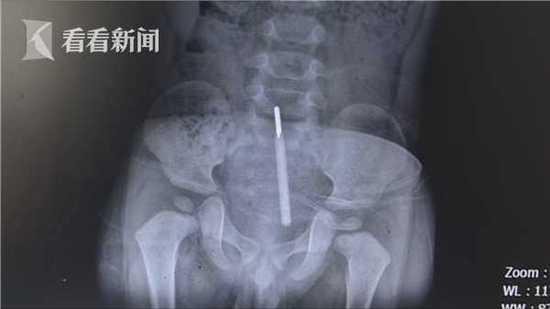

宁波一妈妈给2岁宝宝量肛温,整根水银温度计竟断在体内,捅破直肠!

1岁半男孩测体温不配合一屁股将体温计坐入直肠